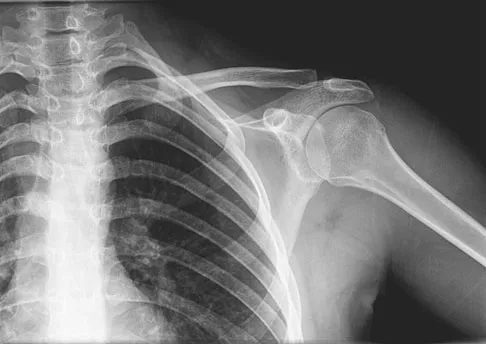

A 70-year-old man who underwent an uncomplicated large rotator cuff repair 6 months ago is now seeking a second opinion regarding persistent pain and weakness in his shoulder. Examination reveals that his incision is well healed and unreactive. The surgical report suggests that the tendons were secured back to bone with sutures through the greater tuberosity. Figure 28 shows a radiograph that was obtained 1 week ago. What is the most likely diagnosis?

Explanation

Symptoms can persist following a rotator cuff repair for a variety of reasons. In the early postoperative period, infection is the primary concern. Stiffness and loss of motion can occur because of postoperative scarring. Complex regional pain syndrome can occur but is rare, and the diagnosis is not made with a plain radiograph. This radiograph shows a superiorly migrated humeral head that articulates with the acromion, indicating that the repair has failed. While large to massive tears may fail more commonly than once thought, the clinical outcome may be satisfactory in many patients. Mansat P, Cofield RH, Kersten TE, Rowland CM: Complications of rotator cuff repair. Orthop Clin North Am 1997;28:205-213.